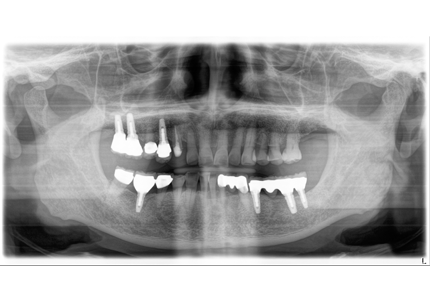

1.初診時口腔内(2007年6月30日)

↑ 2007年6月30日(初診)